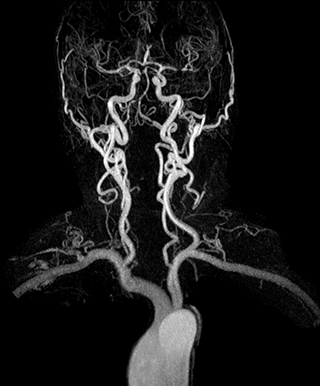

“In our peripheral MRA run-off studies with Ambition we realize key benefits, including outstanding image quality and significantly reduced breath-hold and scan times, which not only benefit the patient, but also provide the opportunity to add sequences that could aid in diagnosis,” Dr. Peña says.

“Before we had Ingenia Ambition, our CE-MRA run-off studies would first acquire a dynamic pre-contrast scan with 20-25-second breath-holds, then inject the contrast, do another acquisition and then subtract the two,” says Avila. “Now, mDIXON XD allows us to complete the study in just one single pass – without need for a pre-exam – which eliminates subtraction artifacts and almost halves the scan time. In addition, mDIXON provides much better background suppression, which really improves vesselto-background contrast. And, thanks to Compressed SENSE, the single breath-hold is not long and we improve image resolution.”

The subtractionless peripheral MR angiography shows improved vessel-to-background contrast and high resolution. Ingenia Ambition 1.5T.

| Station | Ingenia Ambition |

| Pelvis | Voxels 1.3 x 1.3 x 3.2 mm, FOV 430 mm, 125 slices |

| Upper legs | Voxels 1.3 x 1.3 x 3.2 mm, FOV 430 mm, 125 slices |

| Lower legs | Voxels 1.0 x 0.82 x 2.0 mm, FOV 430 mm, 125 slices |

The time saved by Compressed SENSE and mDIXON XD is sometimes used to include additional sequences. An example are peripheral MRA studies, in which Compressed SENSE and mDIXON XD help achieve a 5- to 10-minute reduction in scanning time. This brings the total time down, from the 45 minutes needed with their previous system to about 30 to 35 minutes on Ingenia Ambition, thus providing ample time to include additional sequences.